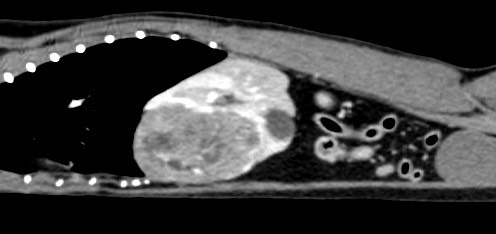

鼻上皮細胞癌

鼻腔症狀是門診中狗貓最常見的主訴之一,但在診斷上卻不那麼容易,在缺乏如電腦斷層、內視鏡、牙科X光等特定設備的情況下,門診醫師多只能嘗試性的給藥觀察,對於慢性、頑固、難治的鼻腔問題往往便束手無策了。

柴犬皮皮因長期有鼻塞、流鼻血、流鼻水的症狀來築心就診,在這之前已經換過兩間醫院,但治療效果都不太好。在一系列的評估後,我們為皮皮安排了電腦斷層以及鼻腔內視鏡的檢查,檢查後發現在皮皮的鼻腔內有疑似腫瘤的團塊,並且向後侵入鼻竇,甚至已經接近大腦。我們運用內視鏡設備採樣取得了團塊的切片,並得到鼻上皮細胞癌的診斷。